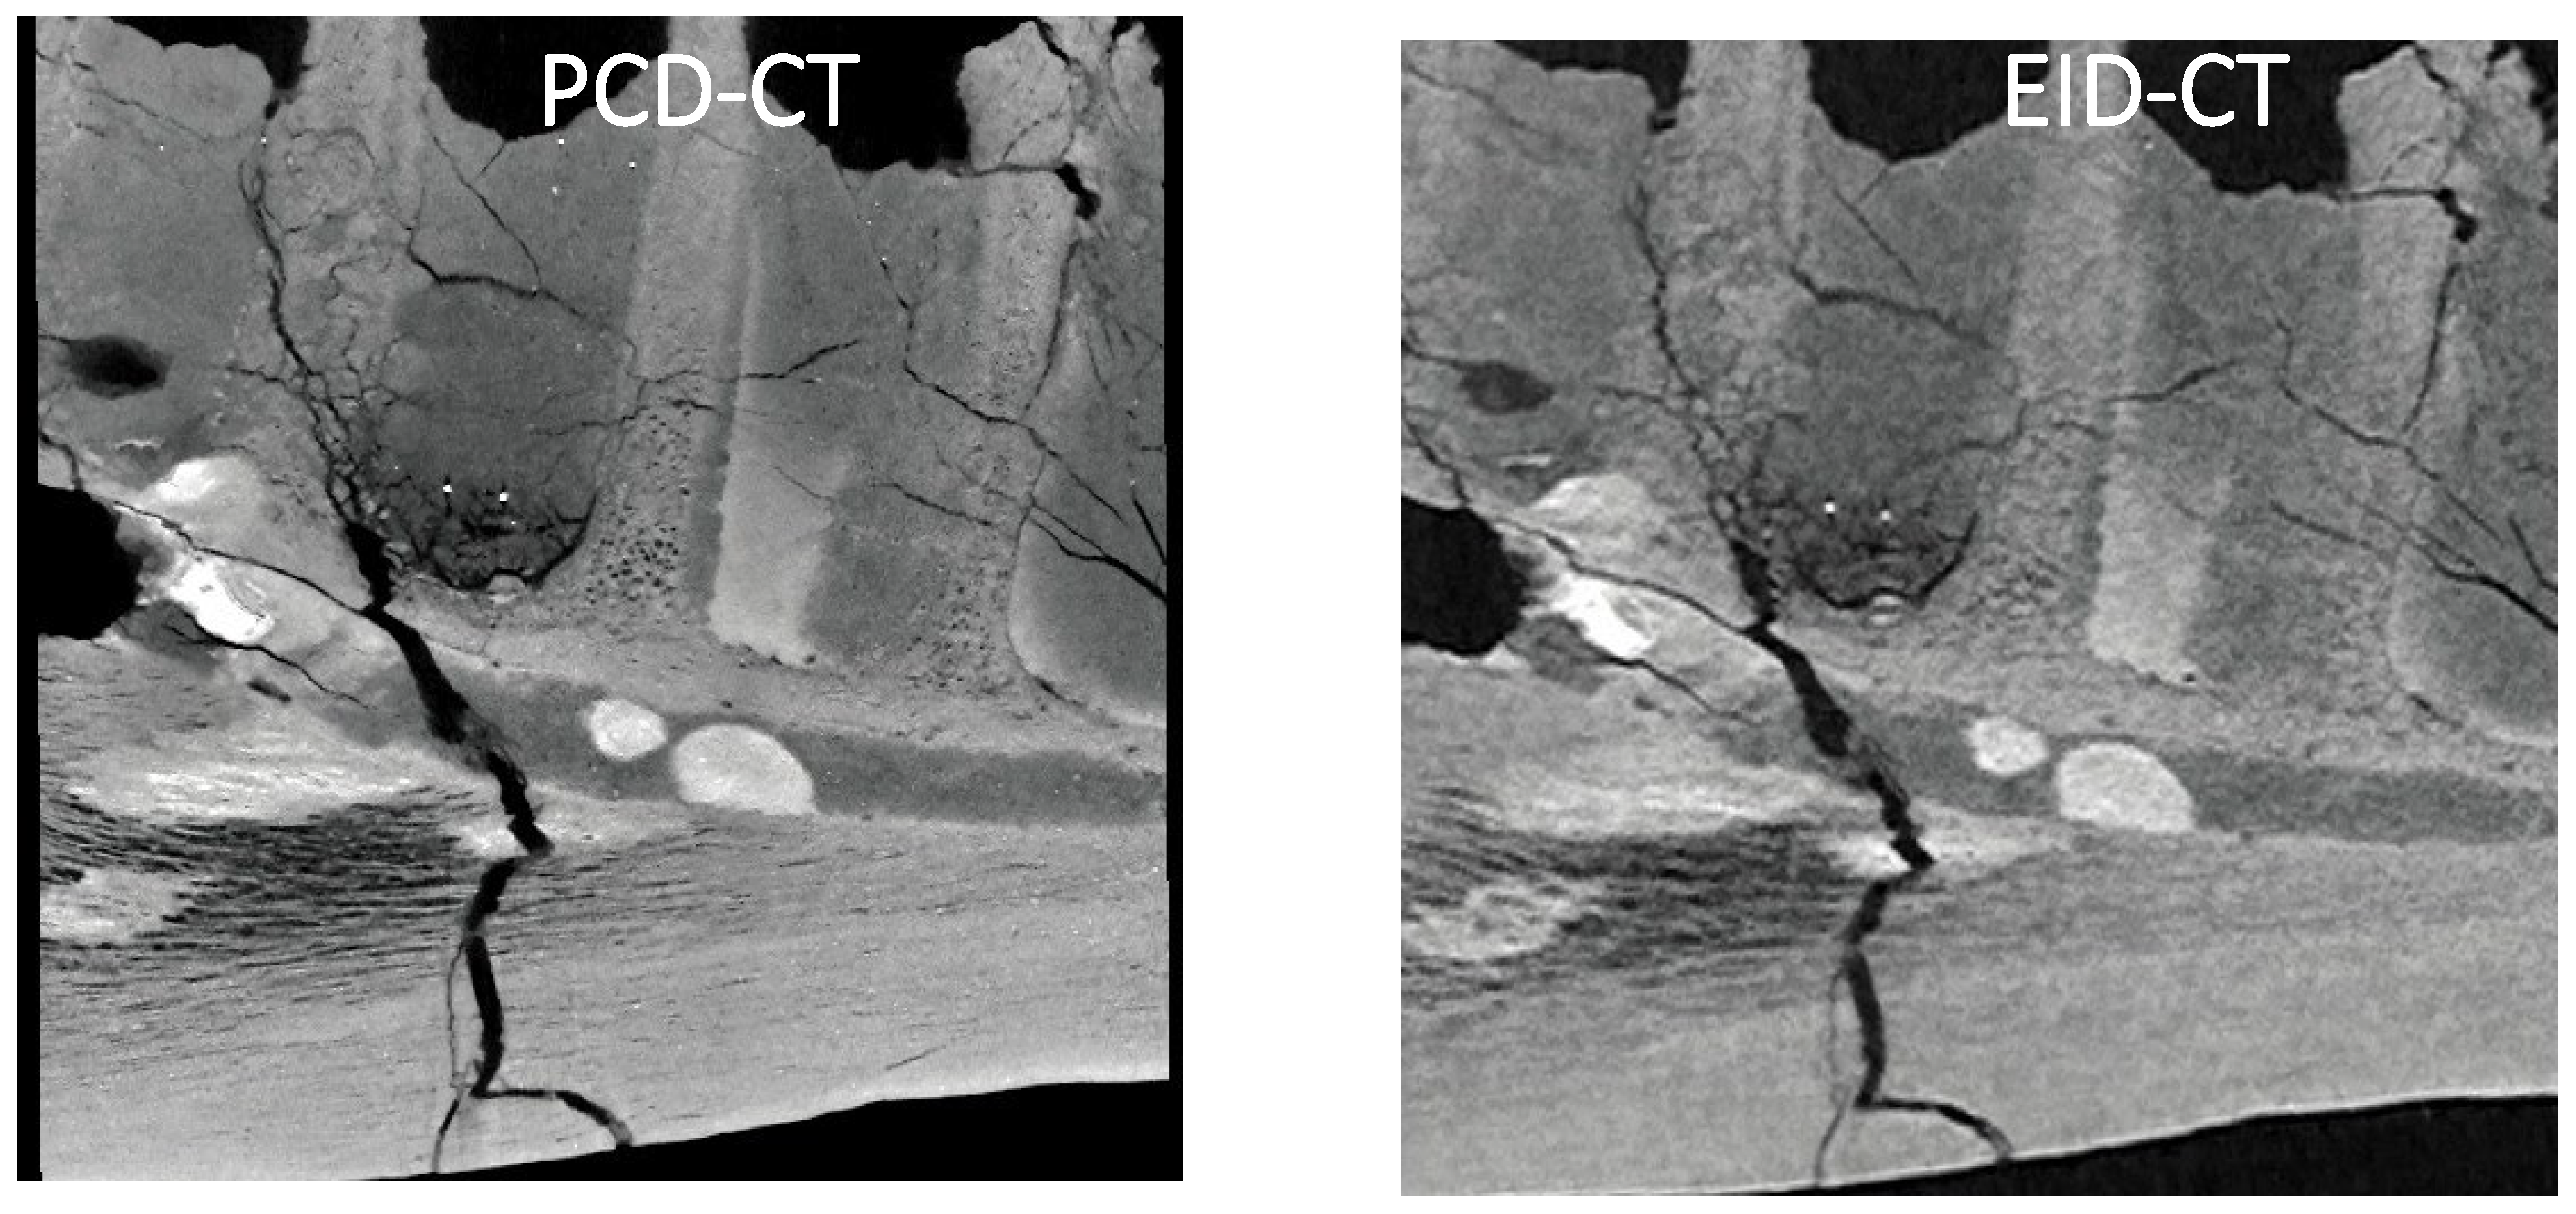

Figure 3A,B show the cross-sections of the Camarasaurus temporal bone imaged with PCD-CT and EID-CT, respectively. Compared with EID-CT, PCD-CT more clearly depicts the selected section of the semicircular canals.

Figure 3. Cross sections of the Camarasaurus temporal bone imaged with PCD-CT and EID-CT.

To the best of our knowledge, this is the first photon-counting CT imaging study of dinosaur fossils. This study demonstrates the significant advantages of PCD-CT over conventional EID-CT in imaging dinosaur fossils. The superior spatial resolution and contrast-to-noise ratio of PCD-CT allow for more detailed visualization of fossil internal structures such as the Tyrannosaurus mandibular canal and the semicircular canals of the Camarasaurus. Visualizing fine anatomical details with PCD-CT creates new possi-bilities for paleontological research. For example, detailed images of the mandibular canal in the Tyrannosaurus fossil may provide new information on the sensory capabilities and feeding behavior of this iconic dinosaur [13]. Similarly, the clear imaging of the semicir-cular canals in the Camarasaurus fossil may shed light on the balance and locomotion of this large sauropod.